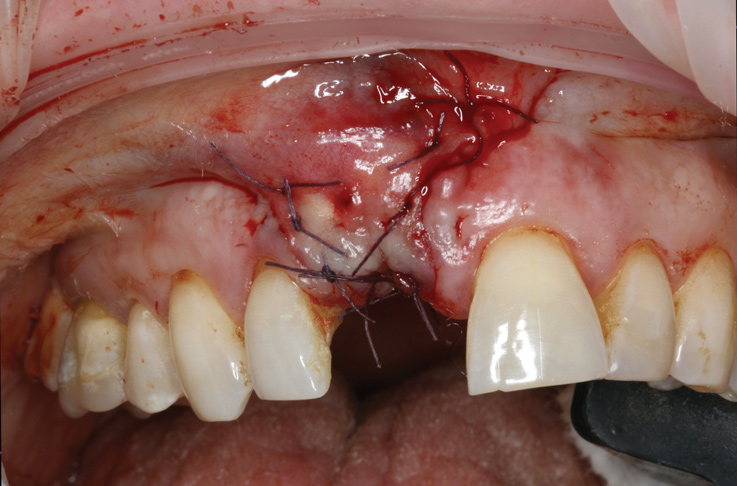

(20.) Tension free primary closure.

Figure 20

Prior to the initiation of the surgery, the surgical guide was tried in to confirm proper seating and stability (Figure 15). A flapless approach was not considered because the need for further bone grafting at the time of implant placement had been anticipated through the digital planning. A slightly palatal crestal incision was made, followed by two vertical incisions on the mesial and distal aspects of the edentulous site in order to preserve the papilla and avoid additional esthetic compromise to the anterior sextant. Next, a full-thickness flap was elevated to facilitate removal of the tenting screw and permit visualization of the buccal plate (Figure 16). A standard guided protocol was followed to place the implant, and its final position mirrored that of the digital plan. As predicted, the prosthetically driven implant position resulted in an insufficient buccal plate (Figure 17); therefore, additional guided bone regeneration was performed to reinforce the area and prevent future breakdown (Figure 18 and Figure 19). Making periosteal incisions could have compromised the blood supply to the flap, so instead, it was stretched in order to achieve tension free coronal advancement.31The flap was secured utilizing horizontal mattress sutures with additional supportive interrupted sutures to ensure primary closure (Figure 20). An immediate postoperative periapical radiograph (Figure 21) and CBCT scan (Figure 22) were taken, demonstrating a final implant position centered with the planned location of the gingival zenith.